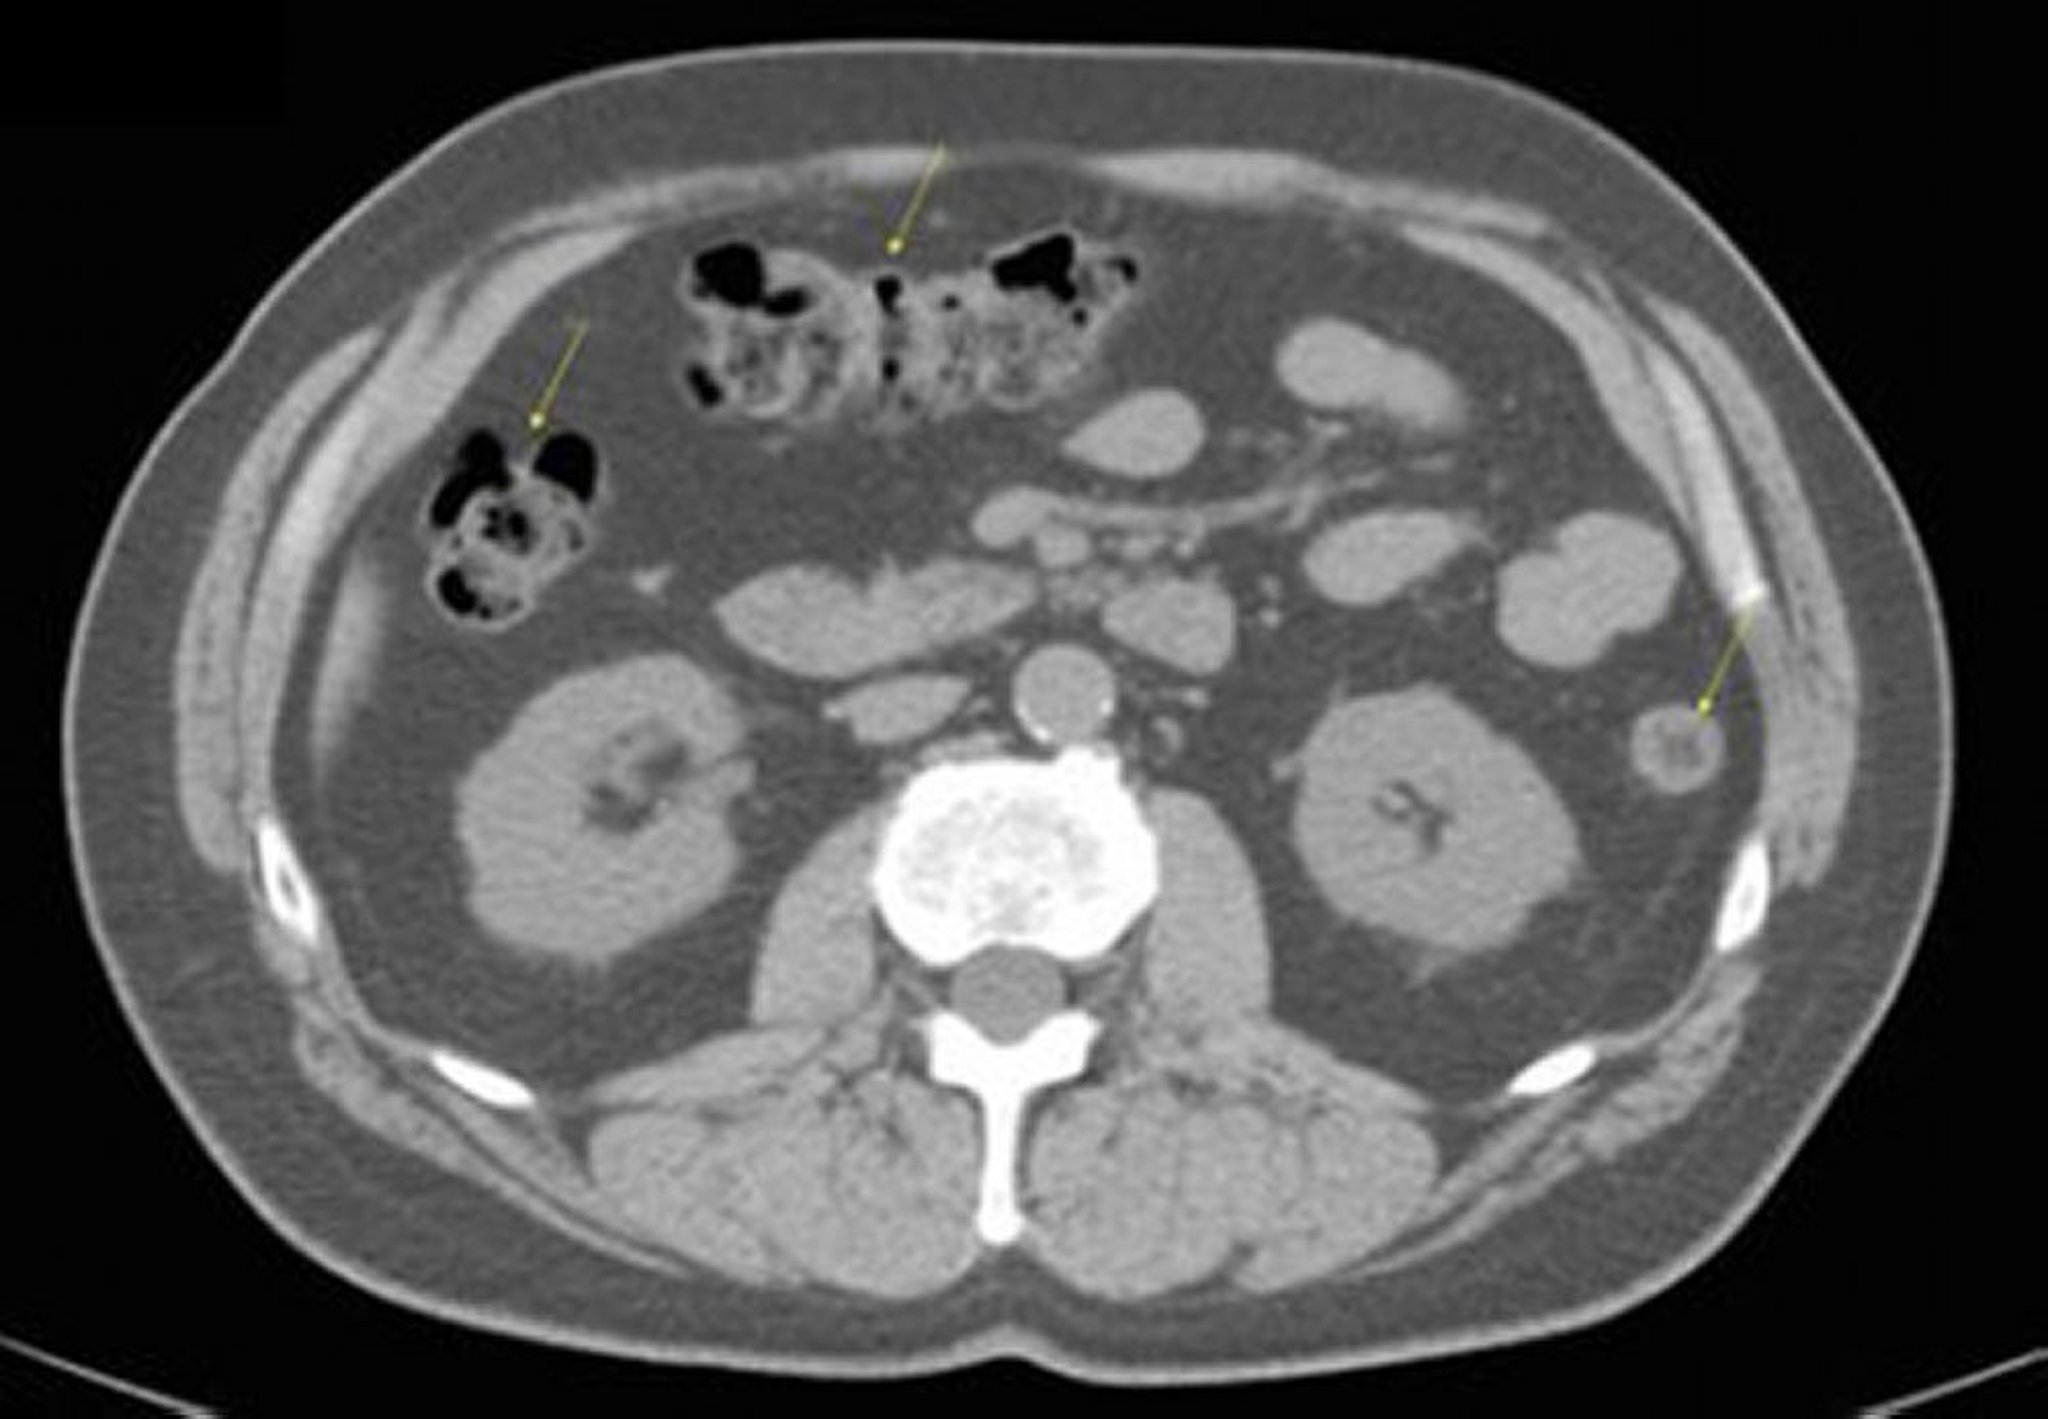

Phim chụp CT vùng bụng và vùng chậu không thuốc cản quang cho thấy giải phẫu bình thường (lát cắt 17)

Hình ảnh này cho thấy đại tràng (mũi tên).